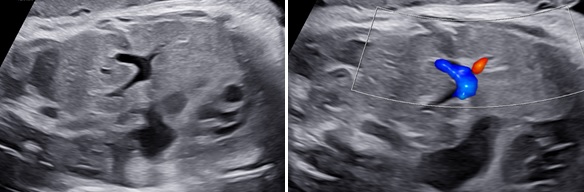

Thoát vị hoành trái: Ở mặt cắt ngang 4 buồng tim có khối phản âm không đồng nhất ở trong lồng ngực trái có thể là dạ dày chứa dịch bên trong (+/-) ruột, gan. Trung thất và tim bị đẩy lệch qua bên phải (Dextroposition). Ở mặt cắt ngang bụng không thấy dạ dày nếu đã bị thoát vị lên lồng ngực.

Thoát vị hoành phải nếu chỉ đơn thuần gan lên có thể khó nhận diện vì phản âm của gan tương tự phổi trên siêu siêu âm thang xám. Hình ảnh đường mật, túi mật là đặc trưng giúp nhận diện gan. Doppler màu có gía trị vì giúp nhận diện các tĩnh mạch gan. Dấu hiệu gián tiếp có thể thấy là hình ảnh trục tim bị lệch.

Hình 2. Thoát vị hoành trái. A: Mặt cắt ngang bụng không thấy dạ dày. B: Mặt cắt ngang 4 buồng tim có hình ảnh dạ dày (DD) và ruột đẩy sát tim qua sát thành ngực phải; phổi phải bị chèn ép.

Hình 3. Thoát vị hoành trái có kèm thiểu sản tâm thất trái